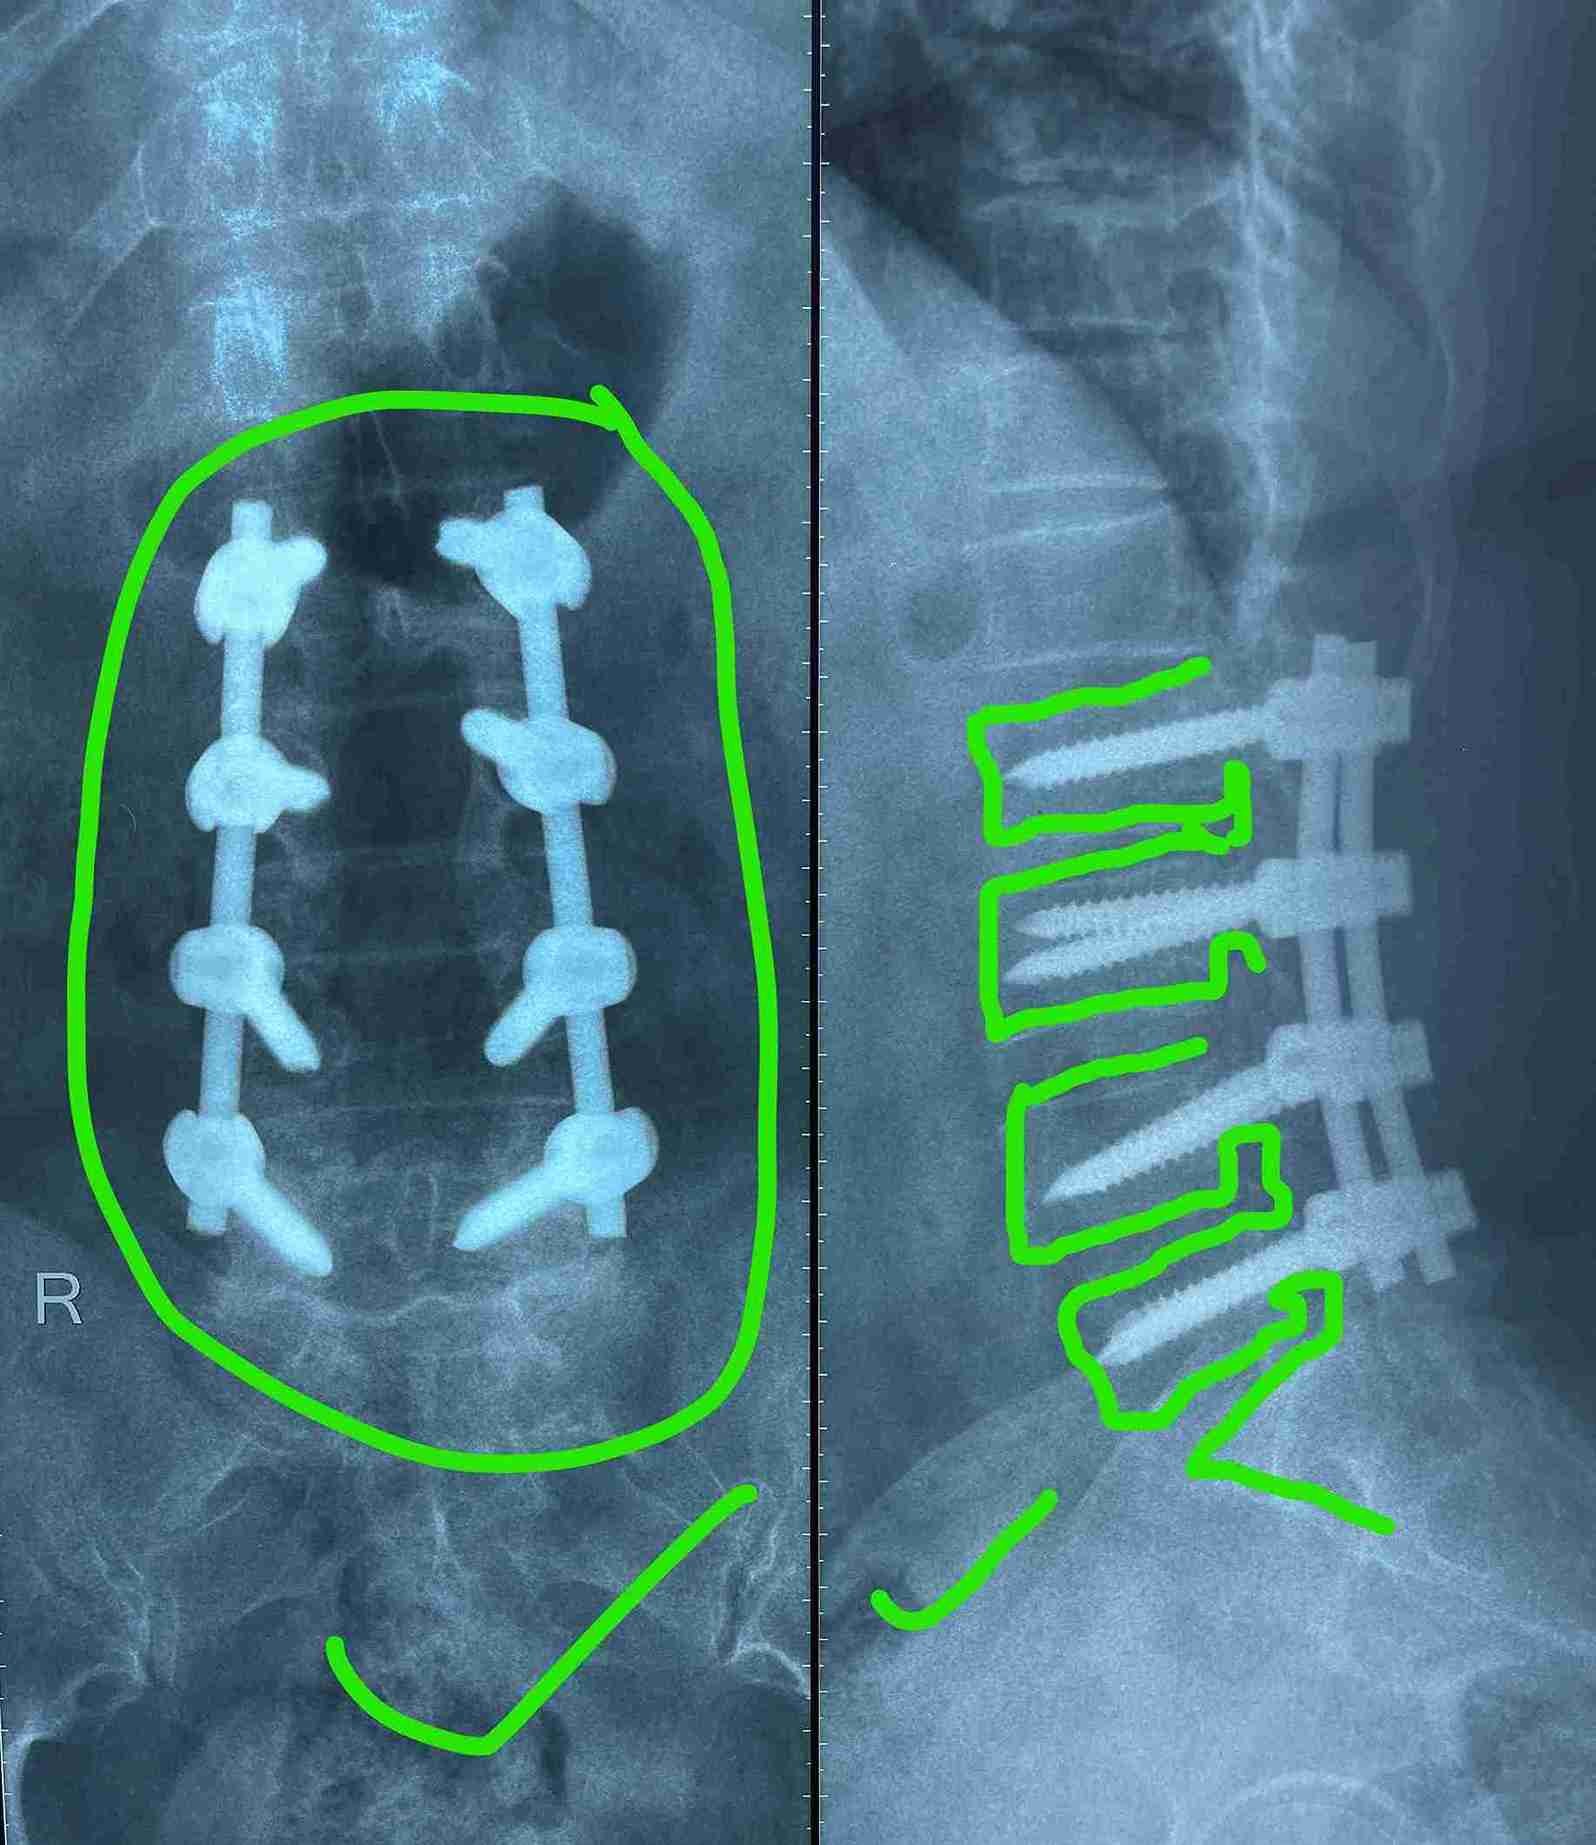

multiple levels of lumbar nerve canal stenosis with spondylolisthesis before and after surgery

A successful surgery was performed to treat multi-level lumbar spinal stenosis accompanied by spondylolisthesis. This condition causes pressure on the nerves in the spinal column, leading to severe pain and difficulty in movement.

• Expanding the narrowed spinal canal at multiple levels

• Stabilizing the slipped vertebrae

• Relieving pressure on spinal nerves

• Use of precision microsurgery techniques under magnification

• Advanced internal spinal fixation